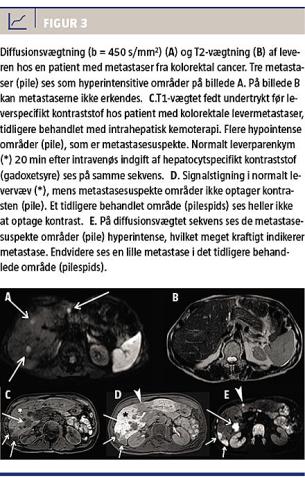

Af leverspecifikke MR-kontraststoffer (ekstracellulære gadoliniumholdige kelater, retikuloendotelialt system-specifikke og hepatocytspecifikke) bruges kun det hepatocytspecifikke kontraststof (fedtopløselige gadoliniumholdige kelater) på de danske hospitaler. Med DW-MR måler man forskelle i mobiliteten af protoner imellem væv (diffusion af intra- og ekstracellulære vandmolekyler). I væv med øget celletæthed som LM

er vanddiffusionen begrænset sammenlignet med i

normalvæv eller i cystiske forandringer. Derfor har DW-MR vist sig at være meget effektiv i påvisning af LM (Figur 3). Sammenligning af DW-MR med konventionel MR har vist en sensitivitet for DW-MR på 83-90% mod 66-70% ved konventionelt MR [25]. Den øgede sensitivitet nedbringer ydermere antallet af falsk positive svar og muliggør bedre planlægning af fremtidige indgreb, eksempelvis leverresektioner.